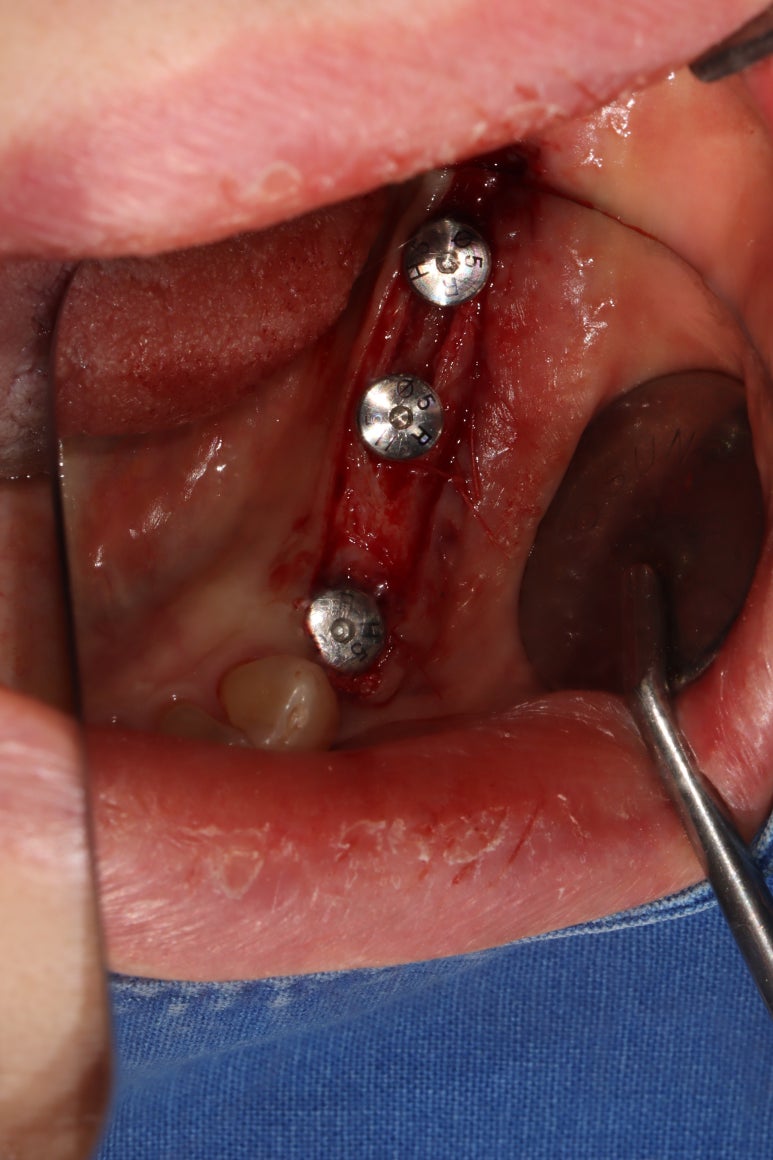

임플란트 1차수술

이렇게 예쁘게 3개의 임플란트를 심어드렸습니다.

뼈이식을 하여야 하는 경우의 임플란트 1차 수술은

치유지대주가 (healing abutment) 아닌 커버스크류(coverscrew)를 장착한채로 마무리 됩니다.

원하는 크기를 선택하여 치유지대주를 연결해 줍니다.

골막 상방에 입천장에서 채득한 두께 1mm의 얇은 유리치은을 이용하여 유리치은이식술을 시행해줍니다.

많이 꿰매지 않기 때문에 시간이 오래걸리지는 않아요.